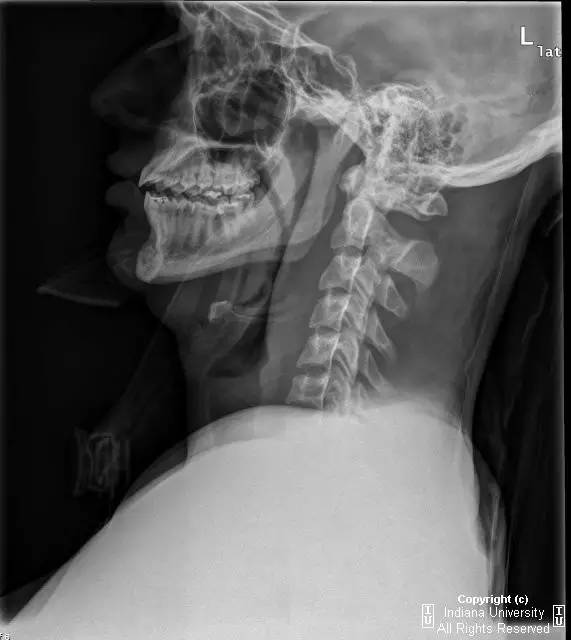

CR: C1侧块相对C2侧块外侧移位约5 – 6 mm,符合Jefferson骨折。椎体周围软组织明显肿胀。MR: 椎体周围间隙可见血肿。覆膜完整。寰枕前韧带断裂。寰枢前韧带完整。左侧横韧带从C1侧块的内侧分离,CT对应在C1侧块内侧见小撕脱骨折。翼状韧带完整。寰枕后韧带完整。前纵韧带和后纵韧带完整。黄韧带完整。

Jefferson骨折(Jefferson fracture)是前后弓均累及的C1环粉碎性骨折。Jefferson骨折为头顶受打击并轴向载荷的结果,力从颅骨经枕骨髁传递到颈椎,C1侧块在枕骨髁和C2上关节面之间被压缩,基于侧块的形状产生向心力而导致C1爆裂骨折。齿状突开口位或冠状位重建CT图像应仔细观察双侧C1和C2关节侧块间有无偏移。虽然C1侧块相对C2上关节面侧方移位提示存在骨折,但在X线片上有时难以发现骨折线。MR可显示相应的韧带损伤。

警告:C1异常时单侧或双侧寰枢椎侧方偏移可达2 mm,而Jefferson骨折通常偏移3 mm或以上。

Jefferson骨折。A,侧位片示C1后弓骨折线(箭)。B,开口位示C1侧块相对于C2偏移(箭)。C和D,轴位CT图像示骨折线通过C1环前、后部(箭)。E,冠状位CT图像示翼状韧带小的撕脱骨折(黑箭)。此图像上也标注了C1在C2上方偏移(白箭)。